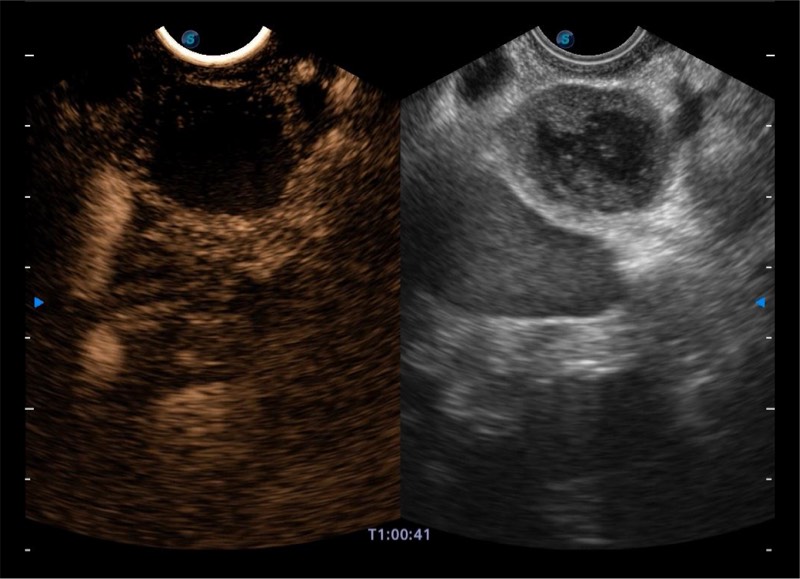

搭载百万级CMOS成像技术

及自主研发凸阵换能器,

可呈现优质的内镜和超声画面

基于二十年的超声技术积累,诸侯快讯官网提供了最新一代的独立超声主机,在提供高质量图像的同时满足多学科使用。具备常见多普勒技术并提供弹性成像、声学造影等高端影像技术。新一代传感器具有更强的抗干扰能力并减少图像伪影。